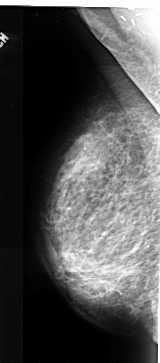

A_1023_1.LEFT_MLO

LEFT_MLO LINES 5431 PIXELS_PER_LINE 2386 BITS_PER_PIXEL 16 RESOLUTION 42 NON_OVERLAY